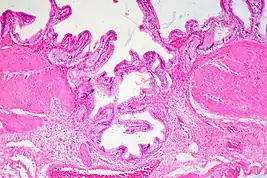

Gallbladder adenomyomatosis is a benign disease of the gallbladder characterized by hyperplasia of the mucosal epithelium and smooth muscle cells inside the muscularis propria.[4][5][6] The excessive proliferation of epithelial cells causes the mucosa to invaginate into the muscular layer lining the gallbladder wall, resulting in characteristic diverticula known as Rokitansky-Aschoff sinuses. These sinuses may be filled with biliary sludge, cholesterol crystals, or gallstones.[4][5][6]

There are three morphologic variants described in the literature – diffuse, segmental, and localized.[5][6] Diffuse, also known as generalized, adenomyomatosis has a widespread distribution of hyperplastic changes and thickening across the gallbladder wall.[5][6] The localized form of adenomyomatosis is also known as a gallbladder adenomyoma (in a similar manner that uterine adenomyoma is the localized variant of adenomyosis). The localized form is a single mass, typically in the fundus, that protrudes into the lumen of the gallbladder in the form of a polyp.[5][6] The segmental form is characterized by its annular (ring-shaped) distribution of adenomyomatosis in the body of the gallbladder, often giving it an hourglass-like appearance.[5][6]